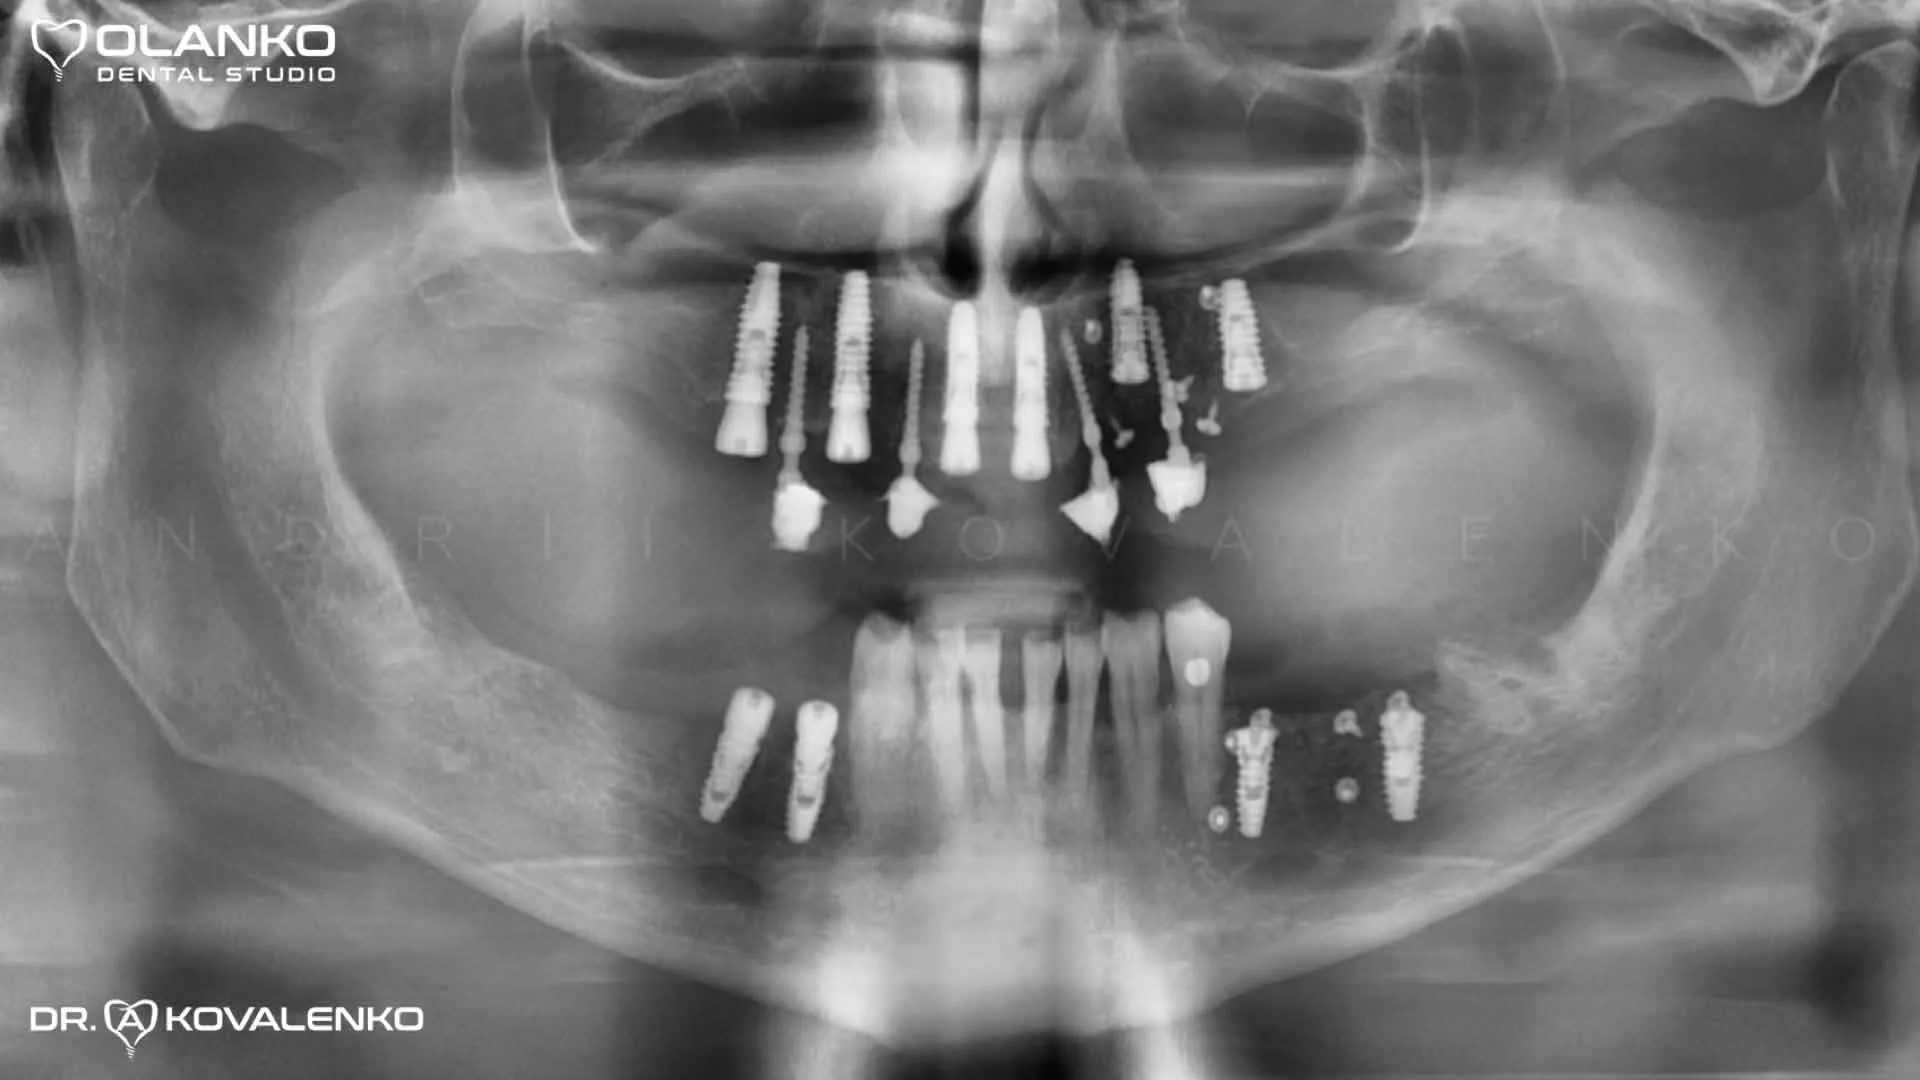

Одномоментно после удаления безнадёжных зубов были установлены десять зубных имплантатов: 6 имплантатов на верхнюю челюсть и 4 имплантата на нижнюю челюсть.

После приживления имплантатов изготовлена цельнокерамическая конструкция из диоксида циркония,  усиленная титановой балкой на верхнюю челюсть и мостовидные конструкции, коронки на зубах и имплантатах на нижнюю челюсть.

Фото панорамный рентген снимок сразу после установки имплантатов

Фото контрольный панорамный рентген снимок после фиксации работы